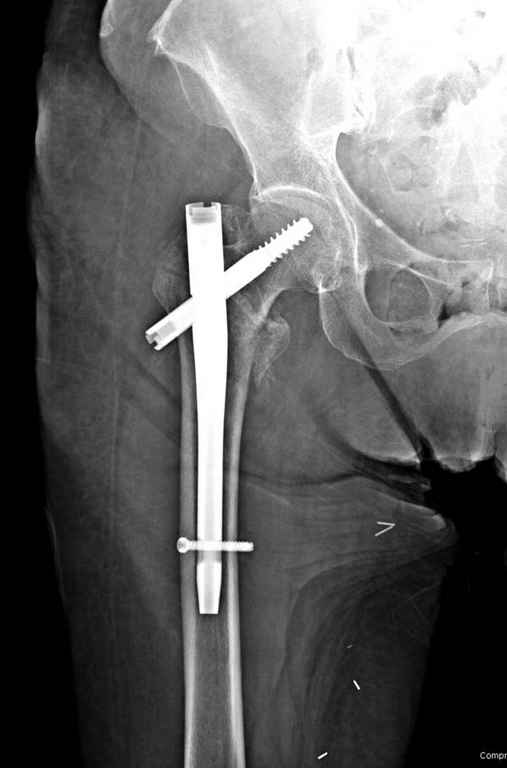

Перелом тут больше подвертельный. Нагрузка без торцевого упора на уровне перелома привела к телескопированию отломков на стержне. Ну и варус небольшой тоже свою лепту внес - если бы его не было, контактирующие латеральные стенки обоих отломков предотвратили бы укорочение, да и срослось бы за пару месяцев. А раз не срослось, упора отломков нет, более слабым местом оказались не нижние винты, а кость в головке и шейке. Так что надо было хотя бы удалить нижние винты до начала полной нагрузки.

На мой взгляд, причиной телескопирования явилось несоответствие диаметра гамма нэйл с диаметром канала подвертельного отдела бедра: обратите внимание на величину протрузии шеечного винта и величину медиализации дистального фрагмента - они одинаковы, смещение или телескопирование фрагментов происходило до того момента, пока гамма нэйл не упёрся в медиальный кортекс и образовалось пространство между латеральным

кортексом и латеральной поверхностью гвоздя.

Диаметр гаммы в диафизарной части ~11 мм. А диаметр канала, тем более у пожилых с остеопорозом, может быть мм 15. Даже рассверливать обычно не приходится, после формирования широкого канала в вертельной области можно сразу толкать гвоздь, он влетает, как карандаш в стакан. Так что соответствия диаметров не бывает никогда. Однако представленная ситуация случается далеко не каждый раз. Если гвоздь в центральном отломке входит чуть медиальнее верхушки вертела, и идет вдоль передне-латеральной стенки центрального отломка, то все будет хорошо.

В приложении похожий пример, к счастью, пациентка появилась не после, а "за полчаса" до протрузии. Пересинтезировали с исправлением ошибок.

Здраствуйте. По данному снимку видно 2-а основных момента которые привели к протрузии винта в вертлужную впадину: 1) шеечный винт дистальной поверхностью наружнего края "зацепился" за латеральный кортикал бедра, это не дало сработать динамической системе гвоздь-винт. 2) лучьше шеечный винт проводить ближе к дуге Адамса, там болееплотная костная ткань. Решенее: как подготовка к эндопротезированию, реостеосинтез, можно такой же системой, но с учетом упомянутых моментов, максимальное безнагрузочное ЛФК (без боли).